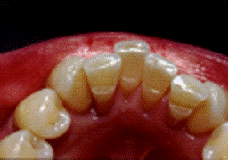

Экстракоронковое шинирование - это

один из самых простых видов соединения зубов друг с другом, относящихся к

несъемному шинированию.

Такая шина изготавливается в одно

посещение в полости рта пациента.

Техника изготовления

экстракоронковой шины:

. Удаляются зубные отложения.

. Шинируемая поверхность

зубов полируется мелкообразивной пастой

. Выверяются окклюзионные

контакты (зубы антогонисты не должны «сбивать» шину).

. Поверхность зуба

протравливается.

. устанавливаются клинья в

межзубные промежутки.

. Нанесение адгезива

(согласно инструкции фирмы-изготовителя) и его полимеризация.

. Нанесение на подготовленную

поверхность зубов композита и его тщательная адаптация соответствующими

инструментами.

. Полимеризация шины на всем

её протяжении.

. Удаление клиньев.

. Финишная обработка шины.

Для данного шинирования также могут

применяться шины из металла, чаще всего не благородных сплавов. Шина крепиться

к зубам с помощью цемент-системы Metabond C&B, Данный метод шинирования

имеет большую прочность, по сравнению с композитным шинированием,

Данный метод шинирования подходит

для фронтальной группы зубов.

Недостатки экстракоронкового

шинирования:

. Возможность нарушения

фонетики (особенно при применение шины на верхней челюсти)

. Затруднение гигиены полости

рта.

. Не надежность конструкции.

Возможны сколы композитного материала.